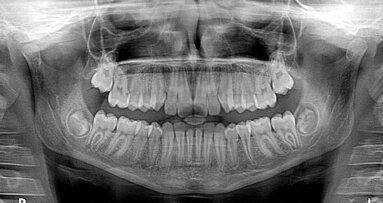

UNIVERSITY PARK, VS – Het is bekend dat bepaalde stoffen die in thee worden aangetroffen, tumorgroei remmen. Toch is er slechts weinig onderzoek gedaan naar theeconsumptie en kankerpreventie en waren de resultaten vaak niet overtuigend. Uit nieuw onderzoek blijkt nu dat een stof uit groene thee specifiek mondkankercellen kan doden.

Onderzoekers van de Universiteit van Pennsylvania deden onderzoek naar het stofje epigallocatechine-3-gallaat (EGCG) dat in groene thee voorkomt. Eerder onderzoek had aangetoond dat EGCG mondkankercellen kon doden, zonder schade aan te brengen aan andere cellen in het weefsel. In deze studie werden in vitro celkweken opgezet van normale en kankercellen door elkaar. Vervolgens werd hier EGCG aan toegevoegd in een concentratie die in speeksel wordt aangetroffen na het kauwen van groenethee-kauwgum. Zo werd een natuurlijke mondsituatie nagebootst; vaak wordt in een testopzet een veel hogere concentratie van de stof gebruikt.

In de cellen werd vervolgens de oxidatieve stress en anti-oxidatieve respons gemeten. Hieruit bleek dat EGCG alléén in de kankercellen vrije zuurstofradicalen produceerde, waardoor de mitochondriën beschadigd raakten en nog meer vrije radicalen vrijkwamen in de cel. Gevolg: alleen de tumorcellen stierven, de normale cellen bleven onbeschadigd. Sterker nog, de beschermingsmechanismen tegen oxidatieve stress werden in de normale cellen juist versterkt door EGCG.

De onderzoekers ontdekten dat het eiwit SIRT3 hierbij een belangrijke rol speelde. In normale cellen bleek meer SIRT3 te worden geproduceerd als de cellen in aanraking kwamen met EGCG, terwijl in kankercellen EGCG de productie van het eiwit juist onderdrukte. Hoe het kan dat EGCG een ander effect heeft op SIRT3 in tumorcellen, is nog niet duidelijk.

De resultaten zijn zeer belangrijk voor de ontwikkeling van nieuwe antikankertherapieën. De huidige chemotherapieën zijn niet selectief voor kankercellen, maar beschadigen ook (in mindere mate) de gezonde weefsels. Als het precieze mechanisme kan worden achterhaald waarmee EGCG onderscheid maakt tussen kankercellen en gezond weefsel, kan dit gebruikt worden om tumorspecifieke behandelingen te ontwikkelen.